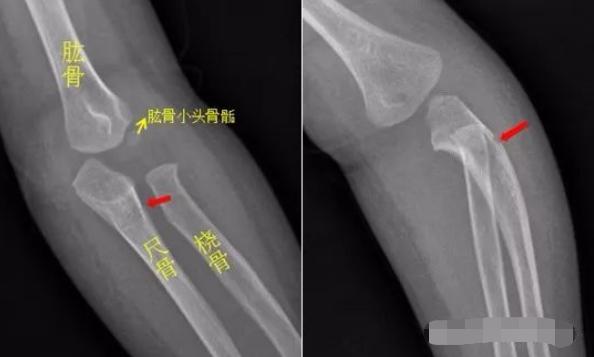

患儿摔倒,右前臂着地,拍片如下:

右侧尺骨中段可见斜形骨折线,骨折端稍分离移位,右侧尺骨中段骨折。